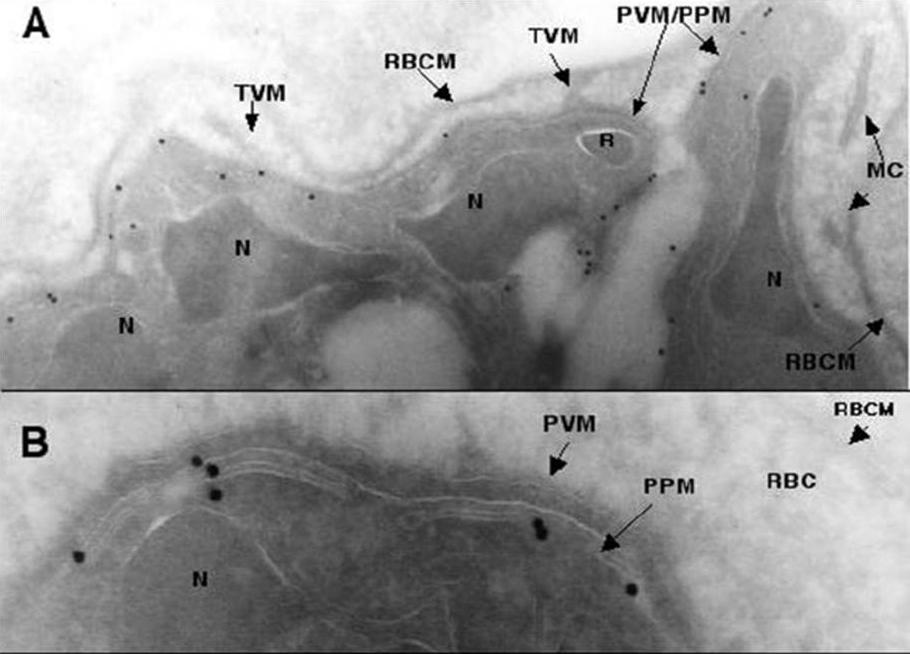

Transmission electron micrographs of ultrathin cyrosections of P. falciparum intraerythrocytic schizont stages using PfNT1 antibodies. Immunogold labeling (15 nm gold particles) of PfNT1 antibodies bound to intraerythrocytic P. falciparum is depicted. Magnification is x 12,000 in panel A and x 50,000 in panel B. MC, Maurer’s clefts; N, nucleus; R, rhoptry; TVM, tubovesicular membrane; RBCM, red blood cell membrane; PVM, parasitophorous vacuole; PPM, parasite plasma membrane.Rager N, Mamoun CB, Carter NS, Goldberg DE, Ullman B. Localization of the Plasmodium falciparum PfNT1 nucleoside transporter to the parasite plasma membrane. J Biol Chem. 2001 276:41095-9.